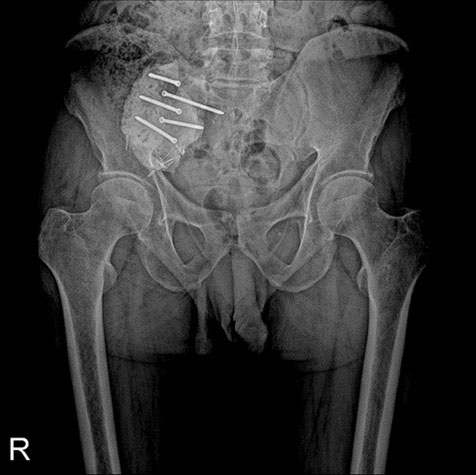

Ameliyat Sonrası: Sağ sakroiliak eklemde vidalar ile tutturulmuş kemik çimentosu